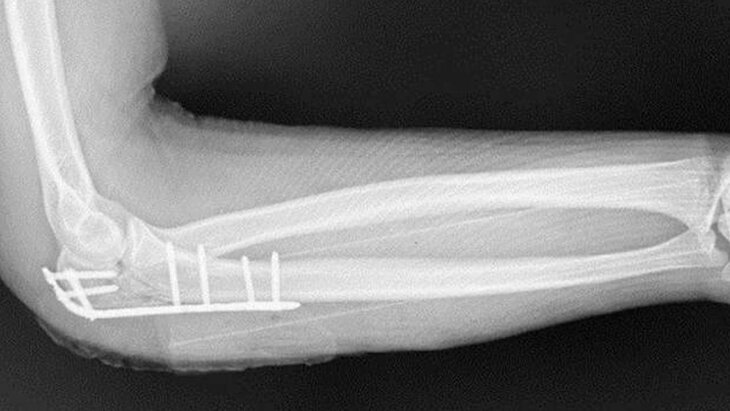

Врачи провели процедуру репозиции, соединив все костные отломки и зафиксировав их в правильном положении с помощью металлической пластины в течение двух часов.

В настоящее время подросток уже выписан домой. Через полгода ему будет удалена пластина, и он сможет свободно двигать рукой.